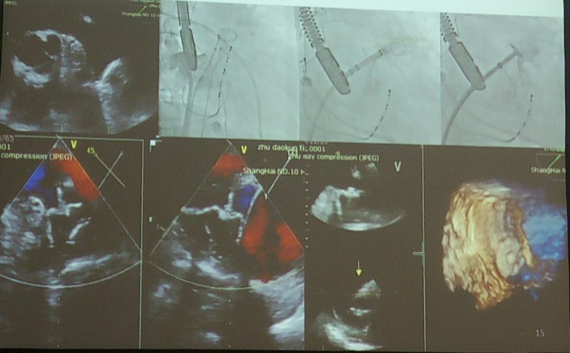

左心耳封堵术的过程

左心耳完成后的情形

术中TEE监测结果(残余分流≤3min认为可以接受)

No leak in 43 patients;1 mm of leak in 13 patients; 2 mm of leak in 11 patients, 5 mm of leak in 1 patients.